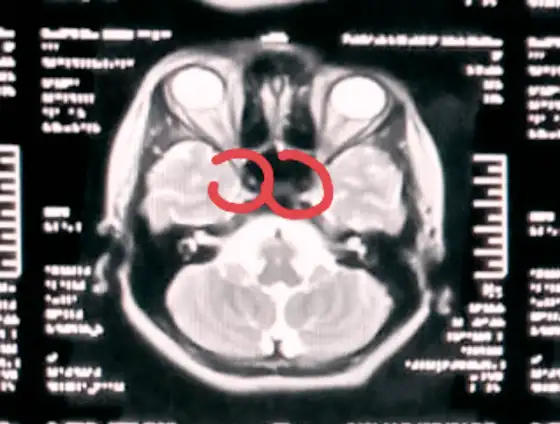

Right and left internal carotid artery circled in red in a T2 axial MRI image